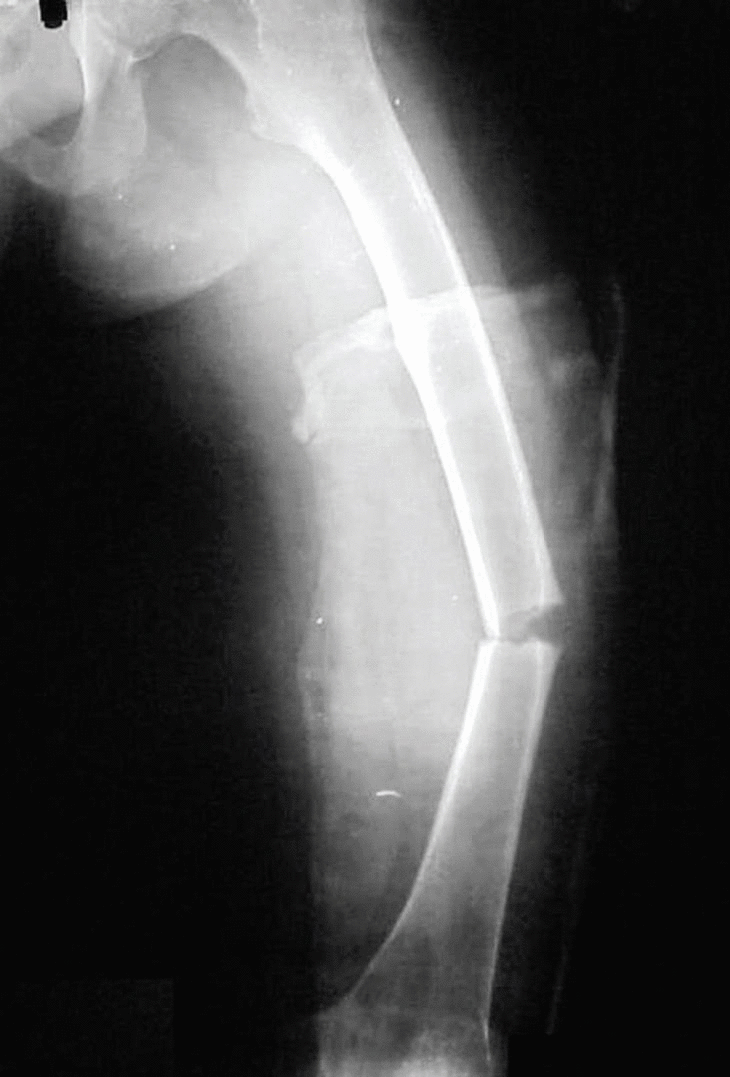

En enero de 2001 ingresa con una fractura del fémur izquierdo que se trata con un clavo no fresado y expansible (FIXION®); en el momento de la introducción se realiza una inserción muy medial y se le fractura la base del cuello femoral, lo cual se resuelve con 2 tornillos de esponjosa (figs.2 y 3). Evoluciona de manera satisfactoria y a las dieciséis semanas existe evidencia de consolidación (figs. 4A y B).

Figs. 4. Dieciséis semanas tras la fractura se evidencia la consolidación por primera intención. A: vista anteroposterior; B: vista lateral.